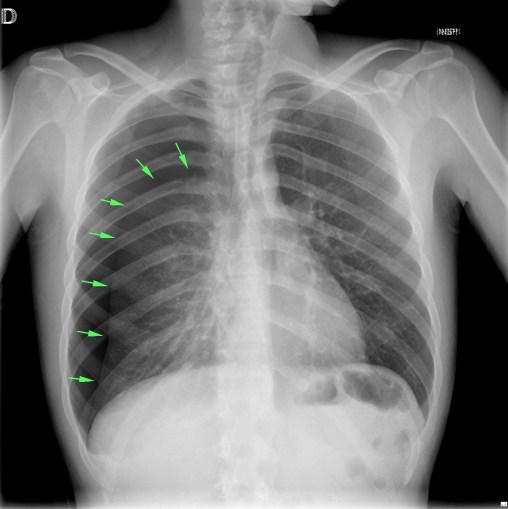

CASO: Dolor súbito en paciente asmático.

- Por la clínica presentada, debemos descartar un posible neumotórax. Sin embargo estamos ante una placa radiográfica con mala técnica.

- Se recomendó volver a realizar la radiografía, observar a continuación:

EXPOSICIÓN:

La penetración es la correcta cuando podemos visualizar la vértebras en su totalidad y las costillas a través del corazón.

El contraste es el adecuado si se pueden difrenciar adecuadamente estructuras con diferentes densidades: partes blandas, plumón y esqueleto.

La definición es buena si conseguimos que el paciente esté totlamente quieto durante la realización de la placa.